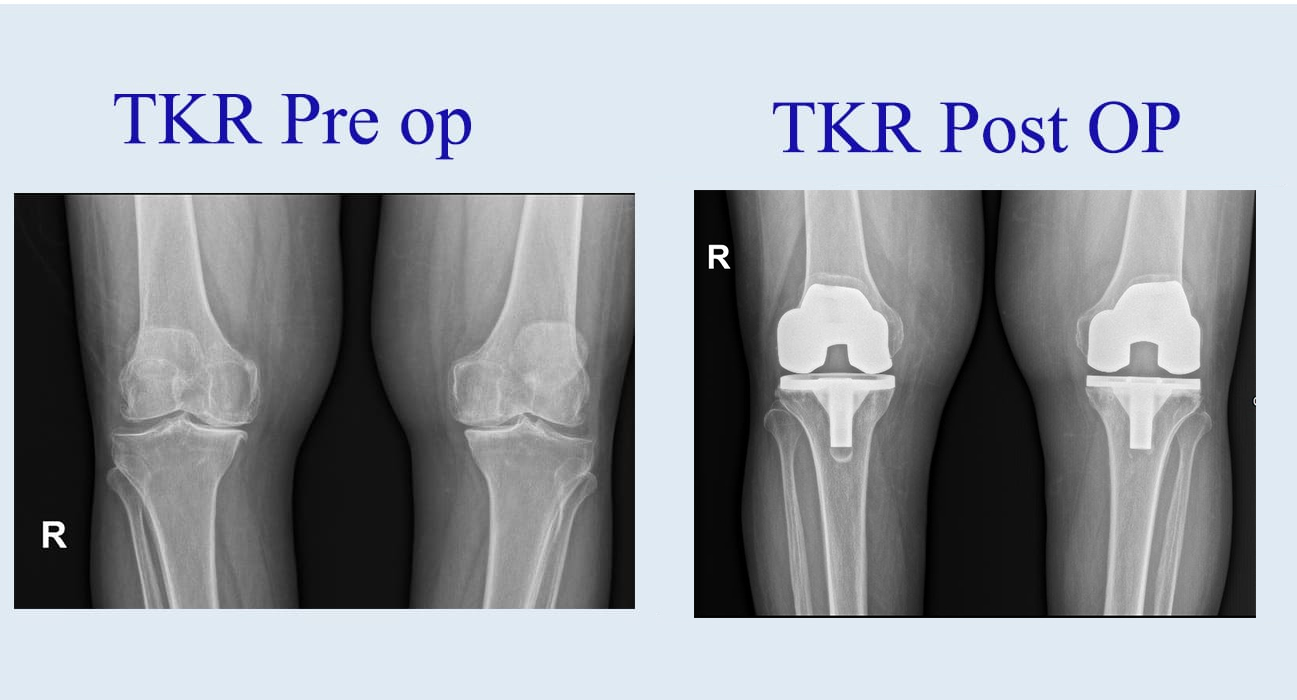

Three major type of arthritis of knee are osteoarthritis, rheumatoid arthritis, and post traumatic arthritis. Osteoarthritis is most common form of arthritis of knee joint. It usually occurs in the age group of 50 years and above due to progressive wear and tear in articular cartilages (cushion) of the joint. Due to the wear and tear of cartilage bone end comes in contact directly and rubbing each other and producing pain in the joint.

Knee pain can be debilitating, affecting mobility, independence, and overall quality of life.

Knee pain can significantly impact a person’s quality of life, making even simple daily activities like walking,